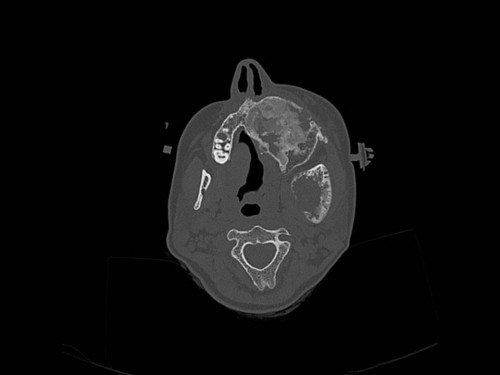

Eine 16-jährige Patientin kommt in eine MKG-chirurgische Praxis zur Abklärung der weiteren Vorgehensweise bzgl. ihrer Erkrankung.

Sie betrachten die angefertigten Röntgenbilder. Welche der folgenden Röntgenbefunde ist korrekt? Ossäre Auftreibungen im Bereich …

- A… der Mandibula links.

- B… des Os frontale links.

- C… des Os zygomaticum links.

- D… des Os temporale links.

- EAlle genannten Aussagen sind korrekt.

Bildgebung - OPAN 2004